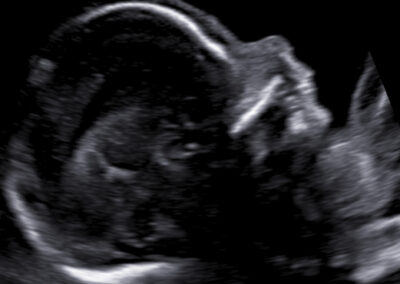

Vyšetření časného těhotenství NT screening Downova syndromu v 1.trimestru Screening vrozených vad ve 2. trimestru Screening ve 3. trimestru